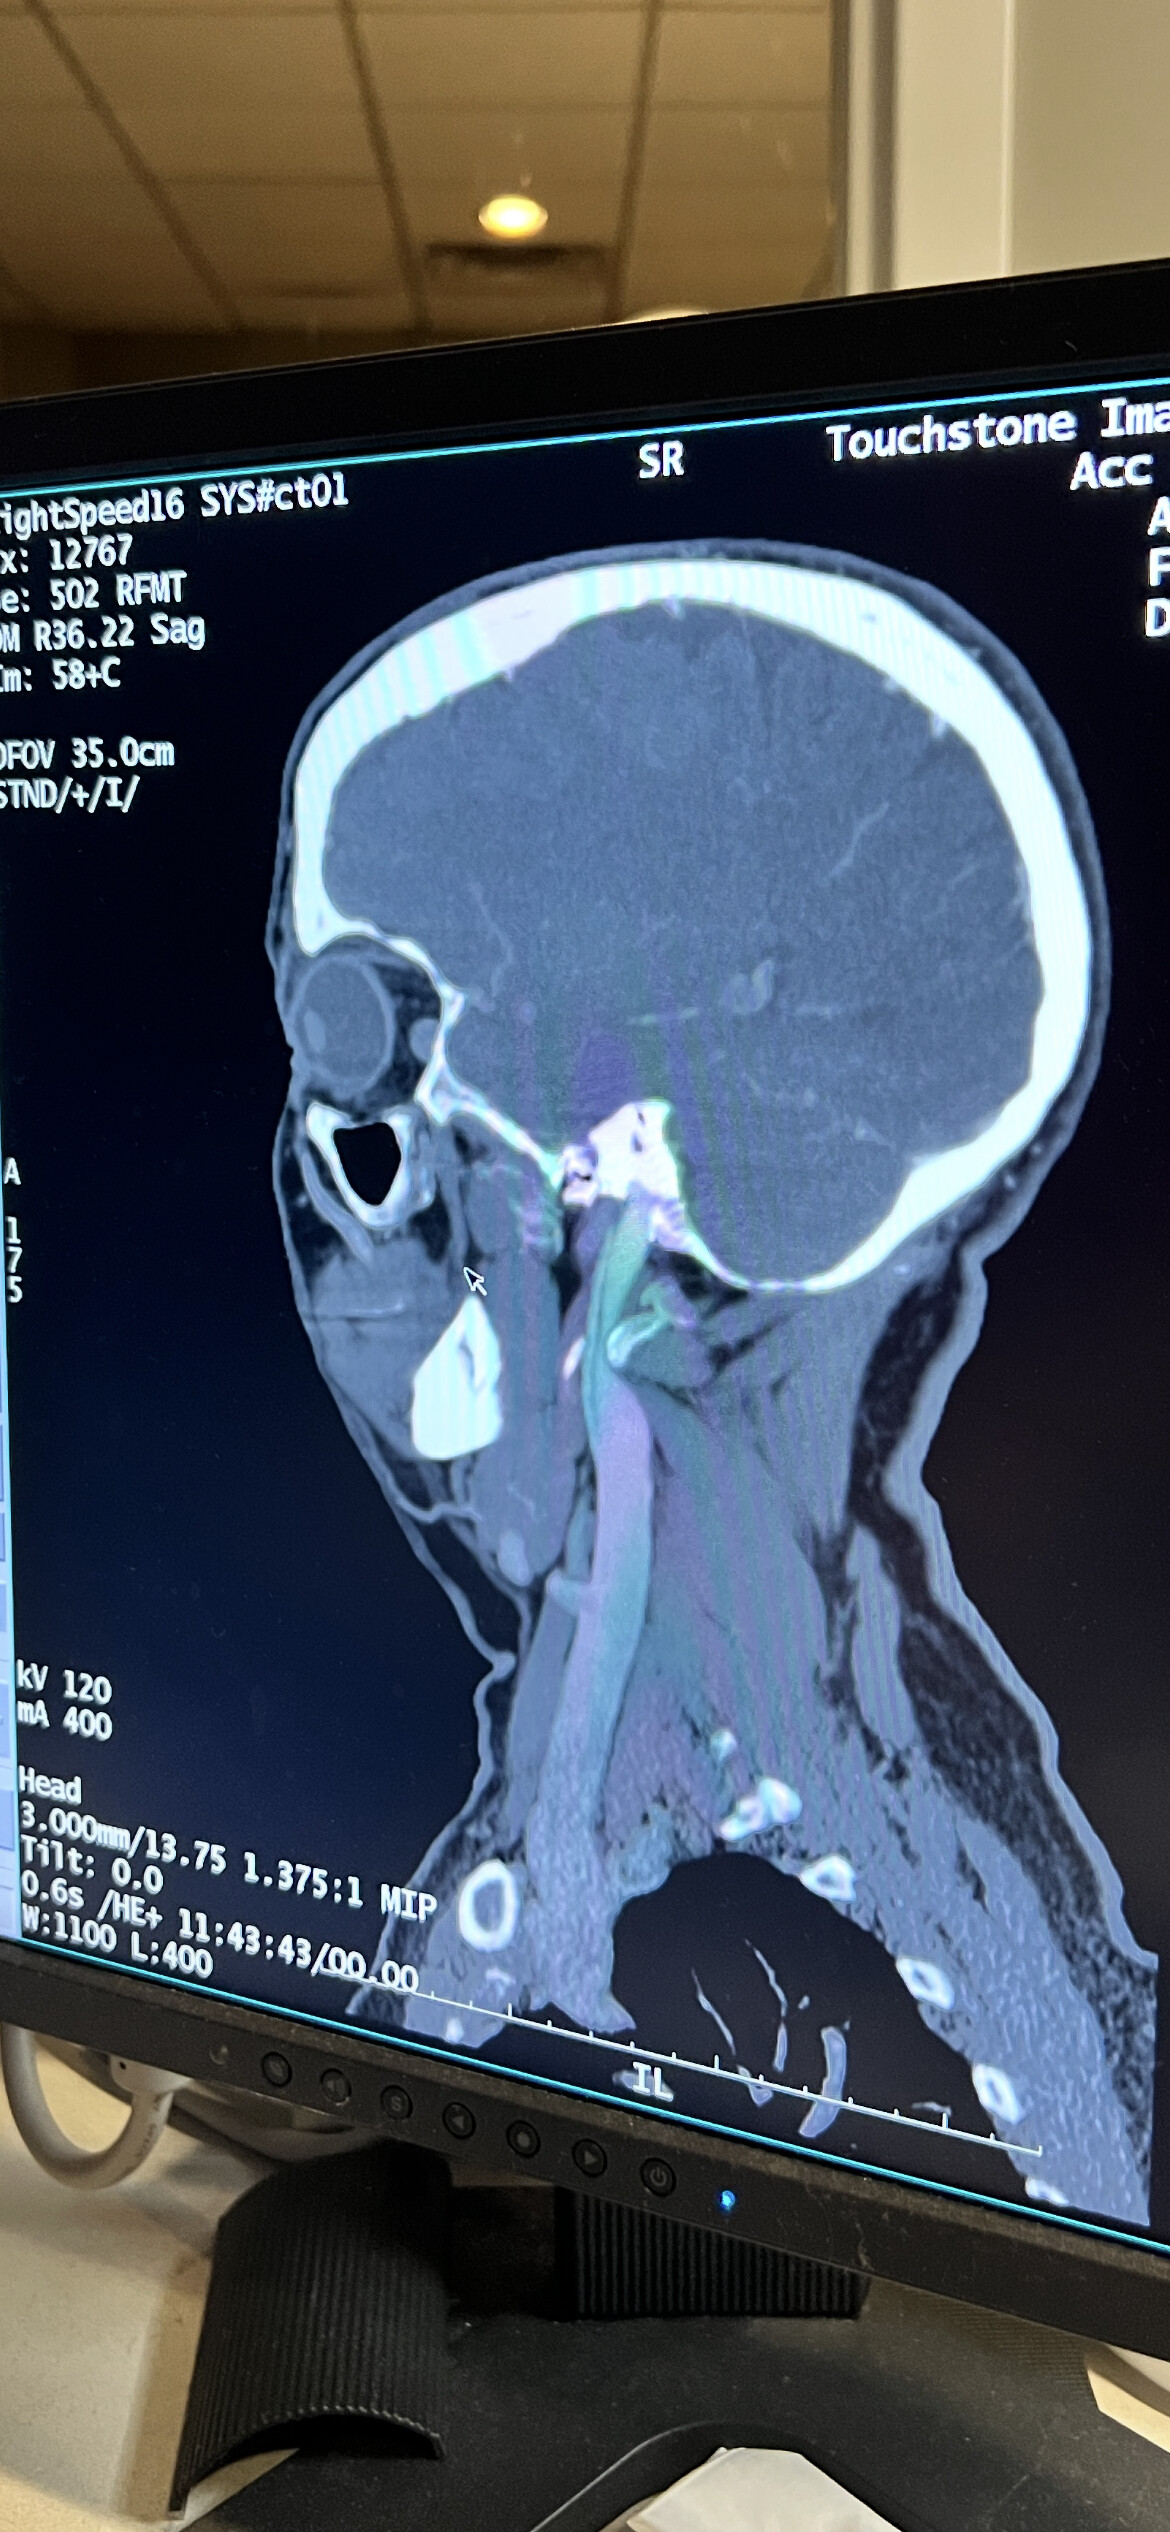

@Minh2025 these are decent views, but not definitive in the role of the styloids. It can be hard to tell from the sagittal view (i.e., the side view that you have posted) how much IJV compression is being caused by C1 vs how much is being caused by the styloids. You do have IJV compression though, just can’t tell from this angle which structure(s) are to blame.

The best view is the axial view of C1. Here’s my own to show you what it looks like. It’s the top vertebrae with a white circle in the top middle: